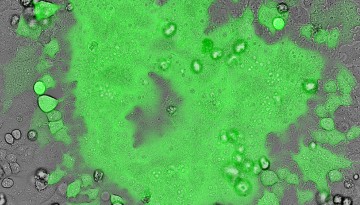

New method drives cellular HIV reservoirs to self-destruct

A research team led by David Russell from the College of Veterinary Medicine has pinpointed a novel angle of attack that could eradicate HIV reservoir cells – while leaving healthy cells untouched.